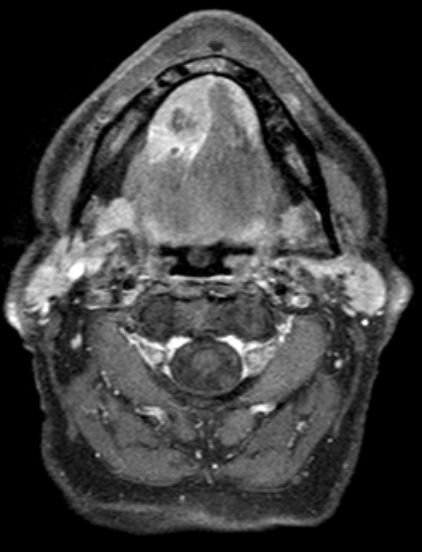

| MRT | 64jährigen Bauingenieur mit einem Mundbodenkarzinom rechts cT4 cN2 M0. Vor 7 Wochen leichte Schwellung unter der Zunge. Am Unterkiefer adhärenter maligner Prozess. Keine Infiltration knöcherner Strukturen. Metastasensuspekter Lymphknoten an der Karotisbifurkation rechts. | ||